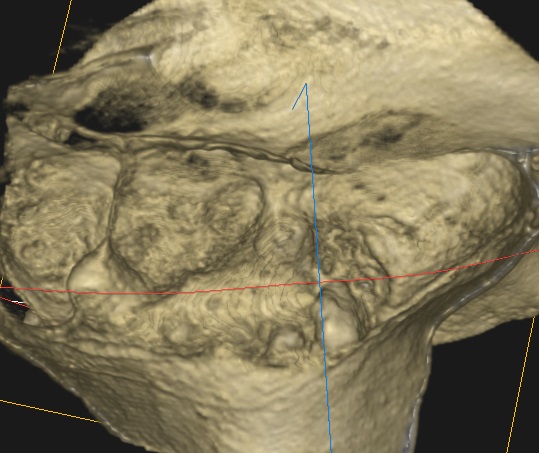

Ryc. 9. Rekonstrukcja 3D – porównanie obrazów zmiany przed i po leczeniu, widok z boku.

Ryc. 10. Rekonstrukcja 3D – porównanie obrazów zmiany przed i po leczeniu, widok z góry.